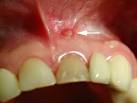

Zahnfistel schmerzfrei behandeln - Berliner Zahnzentrum 9. Meist sind Fisteln im Mund die Folge einer chronisch entzündeten. Fisteln am Zahn zeigen sich häufig zunächst durch Schwellungen am Zahnfleisch, die sich zu Bläschen weiterentwickeln, die gefüllt sind mit). Zahnfleisch Fistel und was zu beachten ist - m Zahnfleisch Fistel: Eine Fistel ist immer ein Zeichen dafür, dass der Körper mit einer Infektion zu kämpfen hat. Regeln für den Masseaufbau - 17. About Calgonate Gel Calgonate First aid for hydrofluoric acid exposure.

Fistel am Zahn (Zahnfistel Symptome, Ursachen, Behandlung)